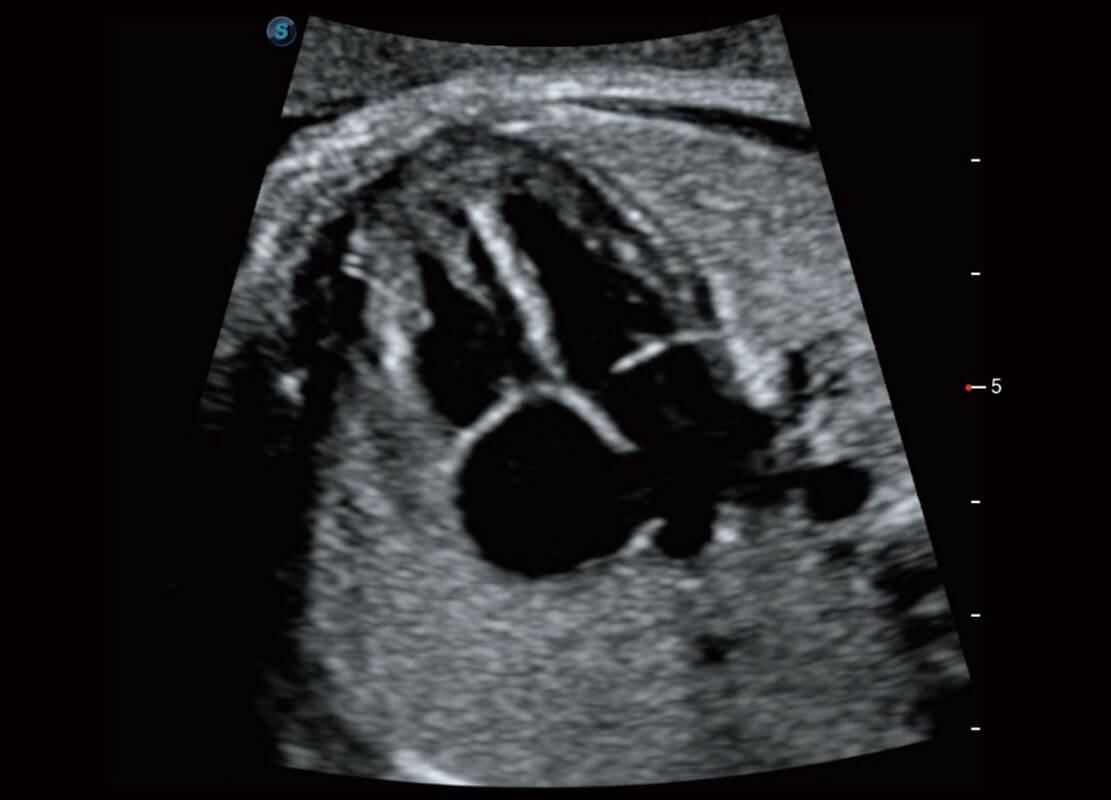

P60优异的图像质量搭载专科探头,在妇科基础疾病的诊断、卵泡生长的监测、输卵管通畅情况的判别等方面为您提供生殖应用方案。

腔内妇科-宫腔分离

腔内妇科-卵巢

腔内三维-宫内节育器

腔内三维-光影成像